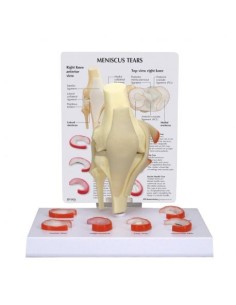

Ginocchio,W47007 modello di lusso